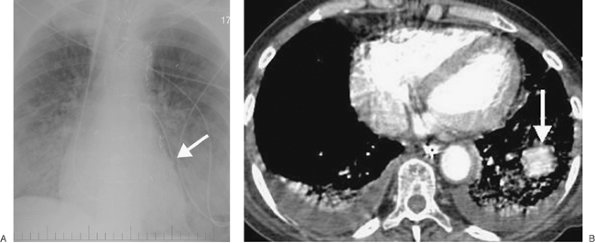

FIGURE 5-11. Pulmonary artery pseudoaneurysm as a complication of pulmonary artery catheter placement. A: AP recumbent chest radiograph in a 66-year-old woman with a history of chronic obstructive pulmonary disease and prior lung volume reduction surgery. The film was taken shortly after right heart catheterization, during which time a pulmonary artery catheter was placed into the right pulmonary artery to measure pulmonary capillary wedge pressure. The radiograph shows diffuse airspace disease in the right lung, consistent with acute pulmonary hemorrhage, which was new compared with a precatheterization radiograph. B: CT scan obtained after administration of intravenous contrast material, performed the same day as the chest radiograph in (A), shows an enhancing peripheral pulmonary artery pseudoaneurysm (arrows), with surrounding pulmonary hemorrhage (arrowheads). The pseudoaneurysm was embolized with coils by interventional radiologists, and the bleeding stopped.

FIGURE 5-12. Pulmonary artery pseudoaneurysm as a complication of pulmonary artery catheter placement. A: AP chest radiograph shows pulmonary edema and the tip of a pulmonary artery catheter projected over an expected left lower lobe segmental pulmonary artery branch (arrow). B: The distal placement of the catheter tip resulted in perforation of a subsegmental pulmonary artery and development of a pulmonary artery pseudoaneurysm, shown as an enhancing mass in the left lower lobe on CT (arrow).